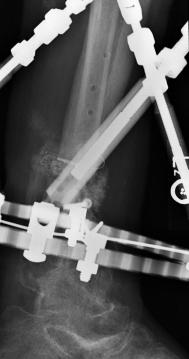

X-Rays and scans of the damaged right & left legs plus the pelvis

These x-rays were taken just after the accident. Some of the bones on the right leg have already been pushed back into the leg. The CT

scans show various views of the ankles and pelvis prior to any corrective surgery. Fibula bracing is clear in some of the images as well as

bracing that was used to secure the "open book" pelvis. In some of the last images it is apparent that the upper part of Liam’s left fibula is

broken. Liam was told that the pain he felt was most likely a muscle cramp. Nothing was done to repair this break and you will see in further

x-rays that the bone shifted and later fused in such a way as to add to the reduction of Liam’s leg length. The last photo shows the stint

used to block any potential blood clots from moving up.